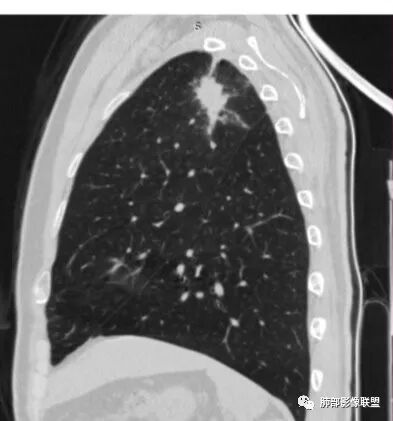

边缘收缩均匀、U型凹陷、内有小点状钙化、桃尖征

支持炎性放前面、

不放心的是部分区域膨隆

2、病灶位于左肺上叶尖后段,符合肺结核好发部位。

3、病灶密度不均,可见钙化点,未显示空洞或液化。边缘收缩,U型凹陷、桃尖征、细长毛刺以及较长棘状突起。宽基底与胸膜相连,邻近胸膜广泛性增厚(未见栽赃侵入)。可见卫星病灶,周围的磨玻璃影比较松散,炎性病变征象多,符合结核的CT表现。

4、部分区域膨隆,未见支气管截断,肺门纵隔未见肿大淋巴结等,恶性征象少。